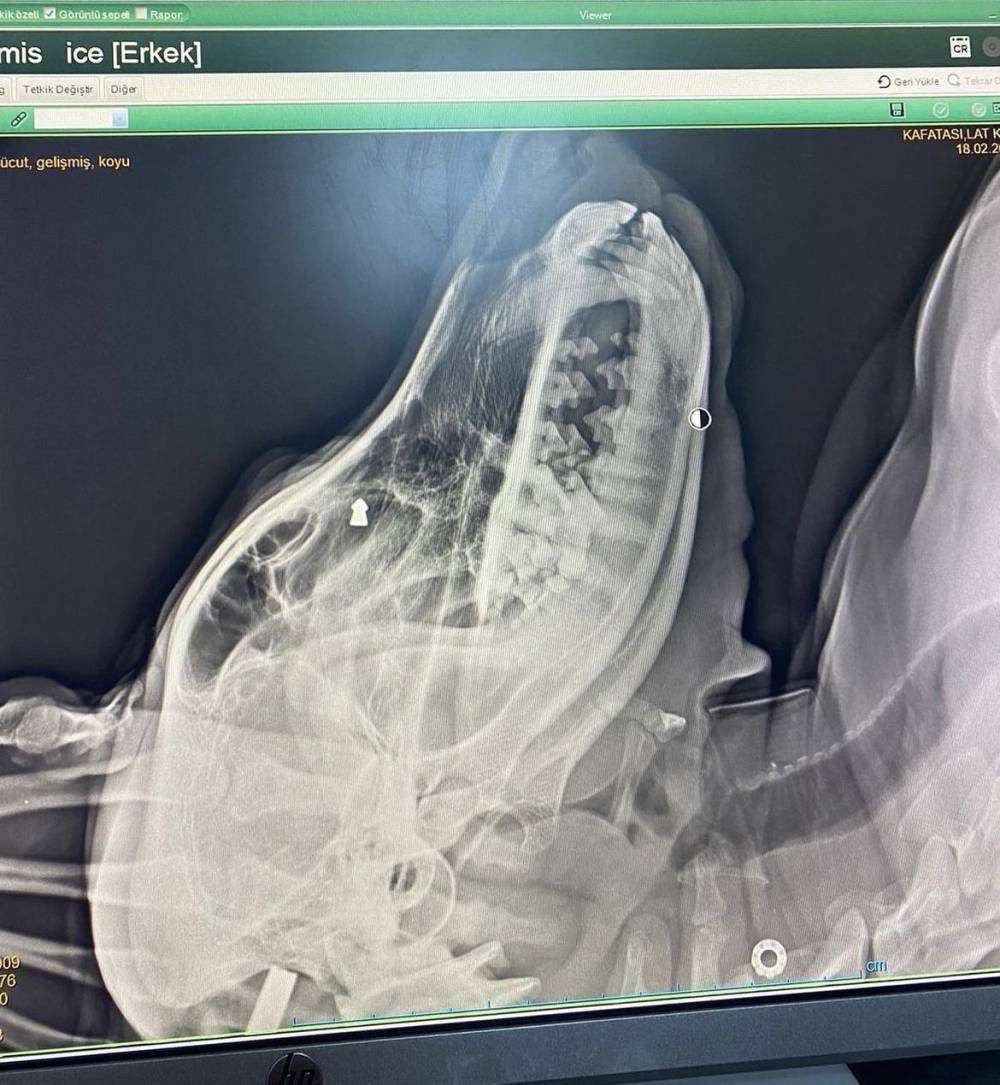

Zonguldak’ın Çaycuma ilçesinde geçtiğimiz aylarda sokak köpeğini silahla vuran şahıs, yakalanarak gözaltına alındı. Köpek tedavi altına alınıp sağlığına kavuşurken, şüpheli ise adli kontrol şartıyla serbest bırakıldı. Olay, ilçenin İstasyon Mahallesi’nde meydana geldi. İddiaya göre, geçtiğimiz aylarda mahallede dolaşan sokak köpeğine, aracında oturan F.K. adlı kişi silahla ateş etti. Ciğerleri parçalanan köpek yol kenarına düştü. Çevredeki duyarlı vatandaşların ihbarı üzerine bölgeye polis ekipleri sevk edildi. Suçunu kabul eden F.K. gözaltına alınırken, yaralı köpek ekipler tarafından veteriner kliniğine götürülerek tedavi altına alındı. İfadesi alınan F.K. adli kontrol şartıyla serbest bırakıldı.

Olay, ilçenin İstasyon Mahallesi’nde meydana geldi. İddiaya göre, geçtiğimiz aylarda mahallede dolaşan sokak köpeğine, aracında oturan F.K. adlı kişi silahla ateş etti. Ciğerleri parçalanan köpek yol kenarına düştü. Çevredeki duyarlı vatandaşların ihbarı üzerine bölgeye polis ekipleri sevk edildi. Suçunu kabul eden F.K. gözaltına alınırken, yaralı köpek ekipler tarafından veteriner kliniğine götürülerek tedavi altına alındı.